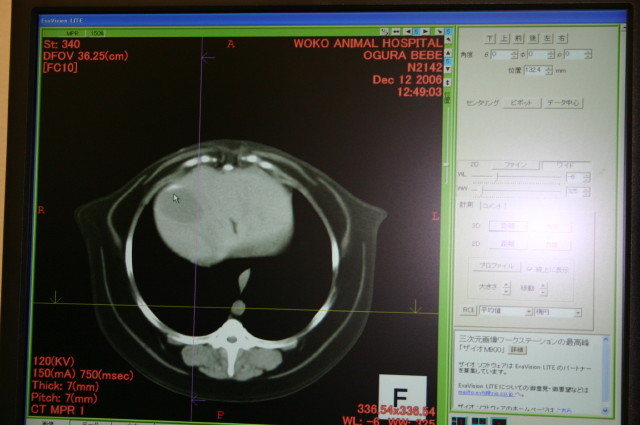

今日の時点での総評としては、『特に悪いところはない』との事(^○^)

【1】フィラリアに罹っていたためか(べべはうちに6歳半で帰ってきた時点ですでにフィラリアの成虫がいて咳をしていた)、年齢のためか肺が白っぽいが、まあ、年齢を考えるとこんなものだし大丈夫でしょうとの事。

(背骨が下)たぶんこれが肺だと思います。違ったらすみません(^^ゞ

【2】胆のうに胆泥が少したまっているが(エコーでも指摘された)、悪さをするような状態ではなく、今すぐ何かをしなくてはならないような状態ではない。問題ないでしょうとの事。

ポインタの先の濃い白いところが胆泥。わかりますか?

5枚目の写真は、今回撮ったCTの一部。

[左]が頭側で、胴体を輪切りにしながら徐々におしり側が写っている。

これが、先生のところのPCのだと、濃度をかえたりしながら、体の中を流れるように見ることができる。